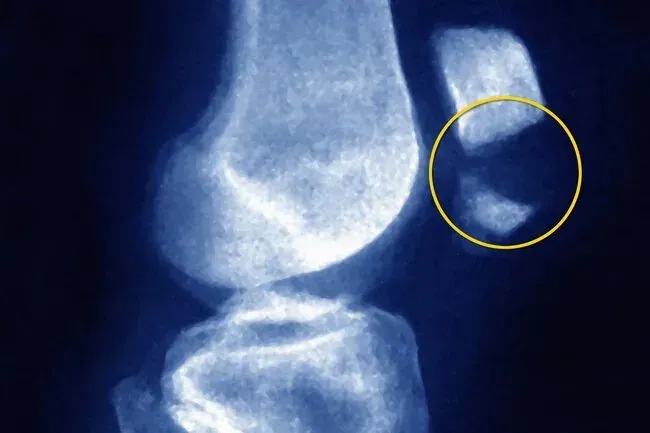

Luxation

Am Ende Ihres Oberschenkelbeins gibt es eine V-förmige Kerbe. Es hält Ihre Kniescheibe und gibt ihm einen Groove, durch den Sie sich bewegen können. Wenn es seltsam geformt ist oder nicht tief genug ist, kann Ihre Kniescheibe herausrutschen. Sie können sogar bemerken, dass es zur Seite bewegt wird. Ein harter Treffer oder Sturz könnte es auch tun. Ihr Knie kann sich anschnallen oder fangen, wenn Sie gehen. Sie werden Schmerzen vor dem Gelenk haben, die beim Gebrauch schlechter werden. Vielleicht hören Sie knarrende oder knackende Geräusche.

Luxation Treatment

Der erste Schritt besteht darin, die Kniescheibe in die Rille am Boden Ihres Oberschenkelbeins zurückzubekommen. Ihr Arzt wird diese Reduzierung nennen. Manchmal passiert es für sich allein. Wenn nicht Ihr Arzt in der Lage ist, es wieder einzuschalten. Wenn es sich nur teilweise verrenkt, können Schienenspangen oder Stärkungspraktiken dorthin zurückkehren, wo es hingehört. Wenn die Versetzung das Ende Ihres Oberschenkelbeins oder die Rückseite Ihrer Kniescheibe schädigt, benötigen Sie möglicherweise eine geringfügige Operation, um es zu reparieren.